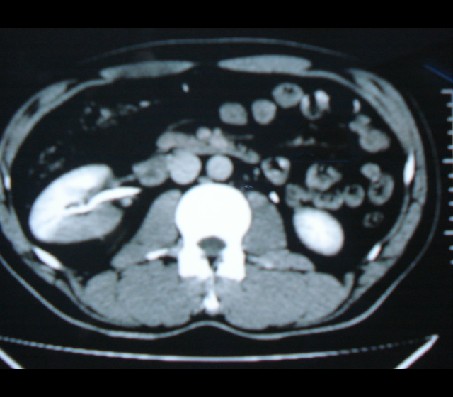

男性,45岁,发现血尿一周。

右肾上极巨大肿块,增强后肿块中度不均匀强化,内见大片无强化液化坏死区,肿块突破肾包膜侵犯肾后筋膜,与邻近腰大肌分界不清,右肾上腺未见明确显示,右肾静脉见充盈缺损,加上本患者有血尿,基本可以肯定为肾恶性肿瘤侵犯肾周伴肾静脉癌栓,此肿瘤为肾癌可能性大。

右肾上极占位(肾癌?)。